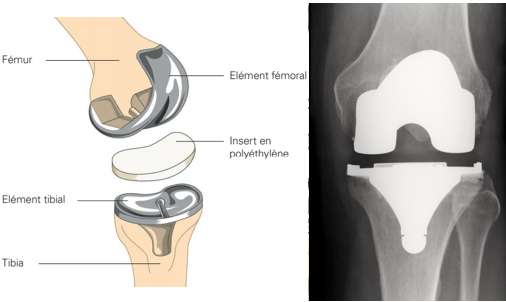

• La prothèse de genou : C’est l’intervention la plus courante pour l’arthrose du genou avancée. Elle consiste à remplacer les parties usées de l’os et du cartilage par une prothèse en métal et plastique. Il existe deux types de prothèses :

• Prothèse partielle / unicompartimentaire : Elle remplace uniquement la partie usée du genou.

• Prothèse totale : Elle remplace toute l’articulation du genou.